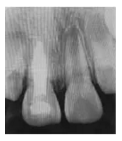

3個月后復診,X線片示:11、21根尖孔未閉合,11根尖部糊劑無明顯吸收,雖根中1/3內吸收未見明顯改善,但根尖孔有閉合傾向,牙根長度開始增加,牙根發(fā)育接近8期,同時發(fā)現11根尖閉合程度略高于21,兩者的牙根長度相近(圖1d)。

圖1d 術后3個月X線片

8個月后復診,X線片示:11、21根尖孔未閉合,11根尖部糊劑無明顯吸收,根中1/3內吸收未見明顯變化。經根尖誘導治療后,11根尖孔閉合程度明顯高于21牙根的自然發(fā)育程度,11發(fā)育接近9期,21發(fā)育8期,兩者牙根長度接近(圖1e)。建議6個月后再復診,待牙根發(fā)育完成、根尖孔閉合后,再完成永久性根管治療。

圖1e 術后8個月X線片